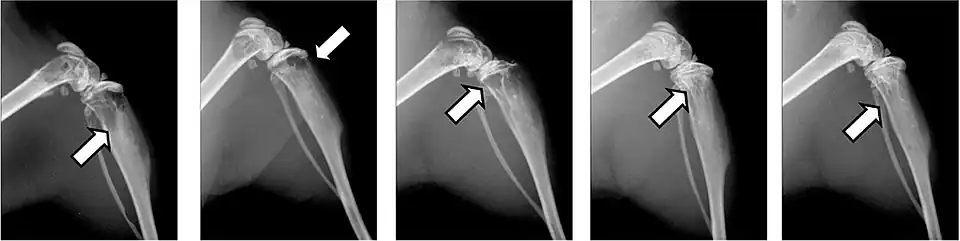

- Aufnahmen pathologischer Frakturen

-

Pathologische Fraktur des Oberarmknochens bei einer Metastase eines Nierenzellkarzinoms -

Pathologische Fraktur des linken Oberarms bei Knochenmetastase einer Patientin mit Brustkrebs -

Ganzkörperknochenszintigramm mit 99mTc-HDP der Patientin mit der Oberarmfraktur aufgrund einer Brustkrebsmetastase